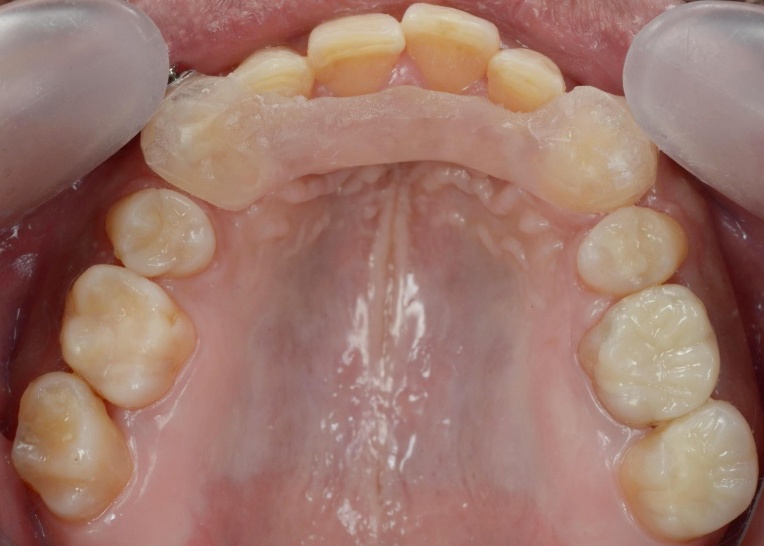

まずはバイト挙上を行います。上顎には、下顎の位置を安定させるための「スプリント」を使用し、下顎奥歯には噛み合わせを調整するための仮歯を装着しました。

そのため、上顎前歯には上顎のスプリントを必要な部分だけカットして歯に直接接着し、噛み合わせの高さを維持するストッパーとして活用しました。

これにより、上顎の装置が矯正のガイド役となり、安定した下顎の位置を崩さずに精密なワイヤー矯正を行うことが可能です。